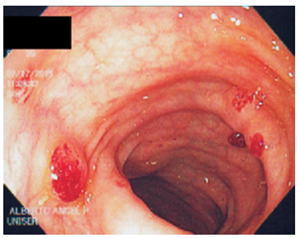

La colonoscopia reporta un pólipo grande en el ciego, de aproximadamente 5 cm de diámetro, que engloba el orificio apendicular, pétreo, del que se toman biopsias. Además, muestra otros múltiples pólipos sésiles de 3 a 15 mm de diámetro, hipervascularizados, con elasticidad conservada, que dan aspecto granuloso a la mucosa a lo largo de todo el colon, incluido el recto. Se toman biopsias. Se hace impresión diagnostica del pólipo gigante en el ciego, para descartar cáncer y poliposis múltiple del colon (Figuras 1, 2, 3 y 4).